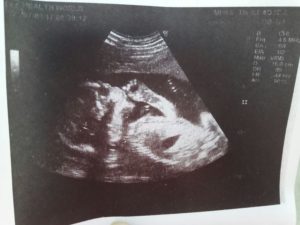

Нередко тонус матки вызывают патологии кроветворной системы, приводящие к сгущению крови. Во всех этих случаях необходимо провести полное обследование женщины. УЗИ с допплерометрией является самым простым способом оценить состояние плода и плаценты.

Ощущаются они как тянущие, ноющие боли внизу живота (похожее состояние в период менструаций), иногда боли в пояснице. Бывает, что женщина не обнаруживает никаких посторонних ощущений в своем организме, но при обследовании УЗИ показывает, что у нее гипертонус матки.

При осмотре живота и влагалищном исследовании тонус матки легко определяется, на УЗИ видны напряженные мышечные волокна. Есть и специальный аппарат для измерения силы сокращения миометрия при беременности, хотя широкого применения он не получил – и без того симптомы состояния слишком заметны.

При прощупывании матки с гипертонусом врач сразу отмечает ее твердость и скованность. Но наиболее информативным методом диагностики является ультразвуковое исследование. Оно безошибочно выявляет локальное или общее утолщение мышечных тканей матки, позволяя оценить обширность и степень тонуса.

Для диагностики используют аппарат УЗИ, также акушеры-гинекологи применяют специальный прибор для более точного определения тонуса матки. Врачи могут воспользоваться простым методом пальпации матки.

Определить локальный гипертонус матки по задней или передней стенке можно с помощью ультразвукового исследования. При этом на УЗИ видно изменение стенки матки в месте её тонуса, она прогибается вовнутрь.